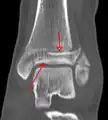

A triplane fracture of the ankle as seen on plain X-ray

A triplane fracture of the ankle as seen on CT

- Tillaux fracture, a Salter–Harris type III fracture through the anterolateral aspect of the distal tibial epiphysis.[14]

- Triplane fractures are a special type of fracture that involves the immature skeleton. It has a coronal plane in the metaphysis, an axial plane in the physis, and a sagittal plane in the epiphysis.[15]